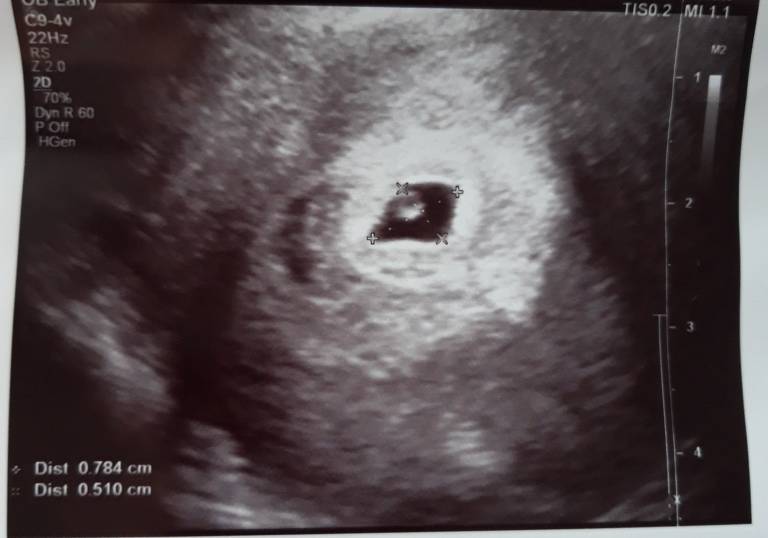

Dziewczyny wczoraj byłam na wizycie u gina po receptę na duphaston ale zrobił mi usg z om 5+1 jest zarodek dobrze umiejscowiony no i kolejna wizyta za tydzień jak to powiedział serduszkowa. Tak wam powiem że pierwszy raz byłam u niego prywatnie zawsze na nfz i nie mogę uwierzyć za wizytę z usg zapłaciłam 50 szok że tak mało bo u innych płaciłem 150-200.

A oto moja kruszynka[emoji7]

A oto moja kruszynka[emoji7] Zobacz załącznik 909345